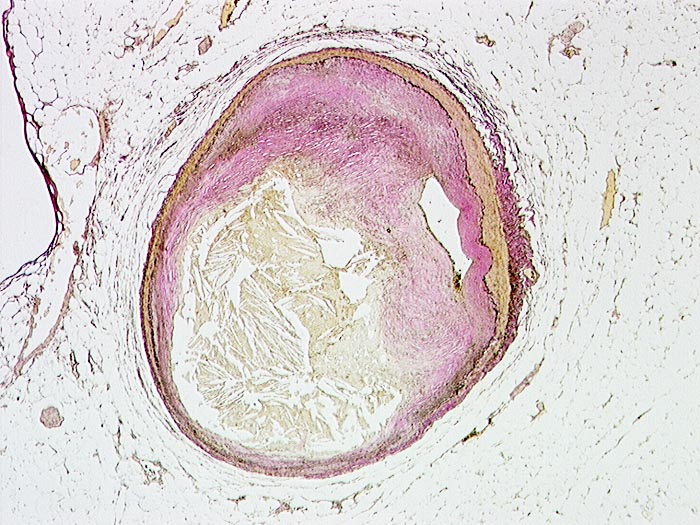

Schwer stenosierende Koronarsklerose

Arteria coronaris

Ein grösseres Atherom und die fibrotische Verdickung der Intima stenosieren das Lumen der Koronararterie. Es besteht eine mehr als 75 prozentige Stenose des Lumens.